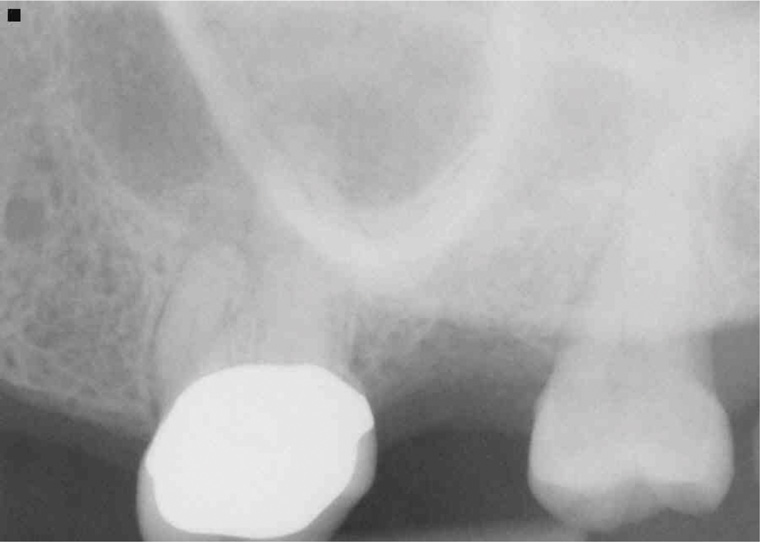

Because of its high resolution and ability to discern between bone and soft tissue, CBCT is the gold standard radiographic exam for the diagnosis of MSEO.2,12,18,20 CBCT imaging provides several advantages over traditional 2-dimensional dental radiographs. On periapical radiographs, anatomic noise imparted by the overlapping structures of the maxillary sinus and zygomatic process can conceal the inflammatory changes associated with apical periodontitis.9,29 Furthermore, 2-D radiographs do not adequately describe the anatomical relationship between the teeth and the sinus floor (Figure 2).3,9

For patients suffering from MSEO, radiographs will reveal a periapical radiolucency with adjacent opacification in the maxillary sinus.12 Additional radiographic findings associated with MSEO include periapical mucositis and periapical osteoperiostitis (PAO). Periapical mucositis refers to mucosal thickening or dome-shaped soft-tissue expansion on the floor of the sinus directly adjacent to the infected root apex.PAO refers to the reactive osteogenesis caused by a local periosteal reaction that expands the sinus periosteum and displaces it upward into the sinus. It appears as a radiopaque "halo" surrounding the root apex (Figure 2 through Figure 4). PAO may be symptomatic and/or accompanied by adjacent mucosal edema and elevated sinus fluid levels.9 If left untreated, PAO can progress and result in a direct communication between the root apex and maxillary sinus.6,13 Unless bilateral odontogenic pathosis is found, the sinus opacifications will usually be unilateral and centered around the odontogenic source. Complete unilateral sinus opacifications may be missed on the CBCT images typically used in endodontics due to their limited or focused field of view (Figure 5). In cases involving complete unilateral sinus opacification, referral to an ENT or oral surgeon is essential to rule out invasive fungal infection or malignancy.2,17,24

(2.) Radiograph of PAO showing necrotic tooth with sinus pathosis obscured by the zygoma.

Figure 2